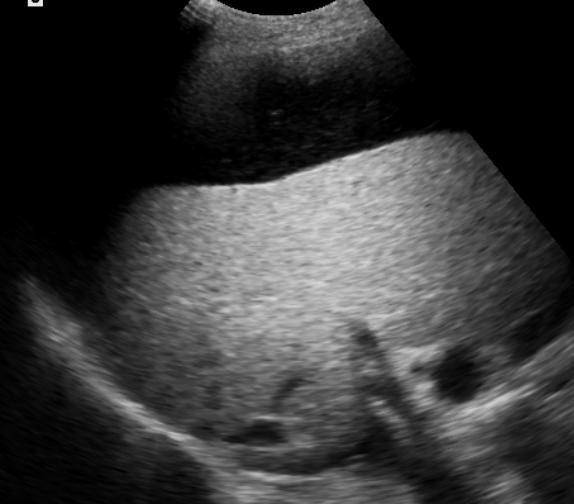

Preprocedural work-up & imaging ![]() 复习所有相关的术前影像资料。关注以下内容 胆道扩张 Dilated bile ducts?

对于熟练的超声科医生,可以清楚地显示胆道阻塞的水平,但MRCP对于阻塞的水平的显示更为直观。胆道是否扩张? 可以通过超声或CT/MRI等影像学容易识别出来